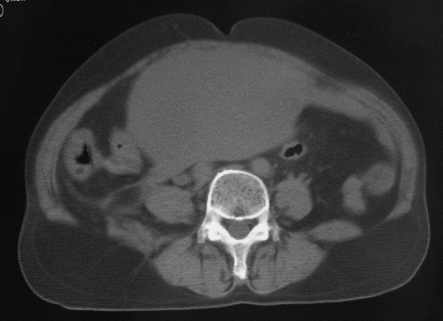

女56岁以右输尿管结石入院

病灶位于下腹部盆腔,从子宫与膀胱明显受压后移看,应该来源于盆腹腔的占位,病灶实性部分密度均匀,左侧可见低密度灶,建议增强扫描,考虑:间叶性肿瘤,或硬纤维瘤,输尿管下段结石伴上段输尿管扩张

右侧盆腔占位,考虑来源于卵巢,囊腺瘤可能性大。

右侧输尿管结石。

1)盆腔占位性病变,考虑来源于卵巢,囊腺瘤可能性大。2)右侧输尿管第二狭窄处结石伴梗阻。

今天病人已经手术证实为右附件囊肿,右侧输尿管第二狭窄处结石伴梗阻!!!

[病理诊断] CT11527:右附件囊肿,右侧输尿管结石。